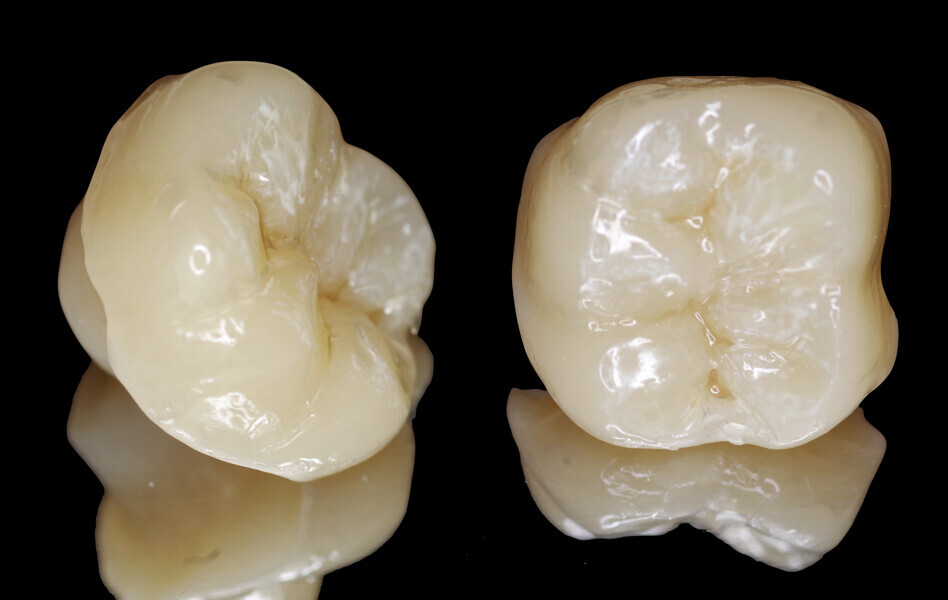

Inner surface of the endocrown. (All image: Drs Alejandro Bertoldi Hepburn & Matías Scazzola)

After general design of the restoration, the impression file was transferred to another design program (exocad) in order to digitally generate the restoration (Fig. 13). After completion of the digital design of the endocrown, the file was returned to the CEREC system. Once this had been done, the restoration was fabricated by milling a block of a highly filled nano-ceramic hybrid material (Grandio blocs, VOCO; Fig. 14). The processing of the composite block took about 10 minutes. Afterwards, a light-polymerising characterisation material (FinalTouch, VOCO) was applied to pretreated furrows and fissures (Fig. 15), light-polymerised and occlusally covered with a packable or flowable composite (or a mixture) and light-polymerised. The endocrown was polished with rubber points and brushes (Figs. 16 & 17).

After several try-in tests, the adhesive luting could take place. For this purpose, the inner surface of the endocrown had been previously roughened through sandblasting with 50 µm aluminium oxide particles at 100–200 kPa, cleaned using brushes and distilled water and detergent, rinsed with water and dried with air stream (Fig. 18a). Thereafter, a silane coupling agent (Ceramic Bond, VOCO) was applied and let dry for 60 seconds (Fig. 18b). Once again, retraction cord was placed in the gingival sulcus to displace the free gingivae and prevent fluids from affecting the adhesive process, and Teflon tape was used to protect the neighbouring teeth (Fig. 19).

Figs. 18a & b: Inner surface of the endocrown after sandblasting with aluminium oxide particles, followed by cleaning of the surface with distilled water and detergent (a). Application of Ceramic Bond (b).